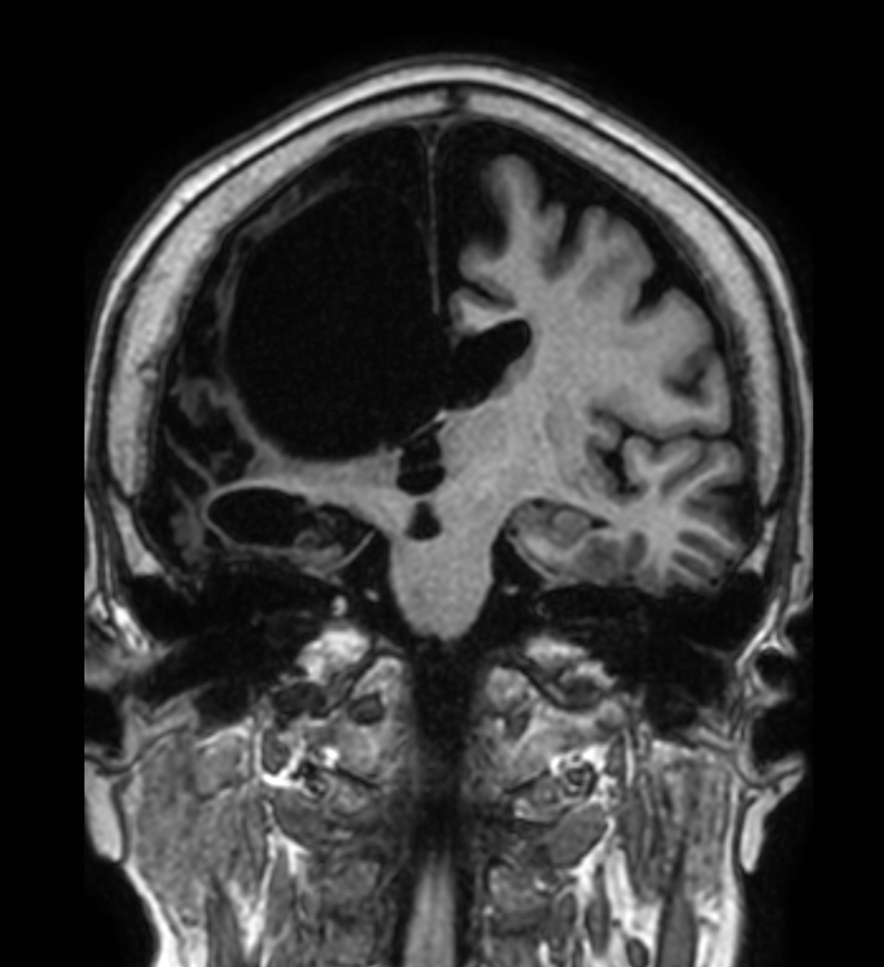

Coronal T1w 3D TFE